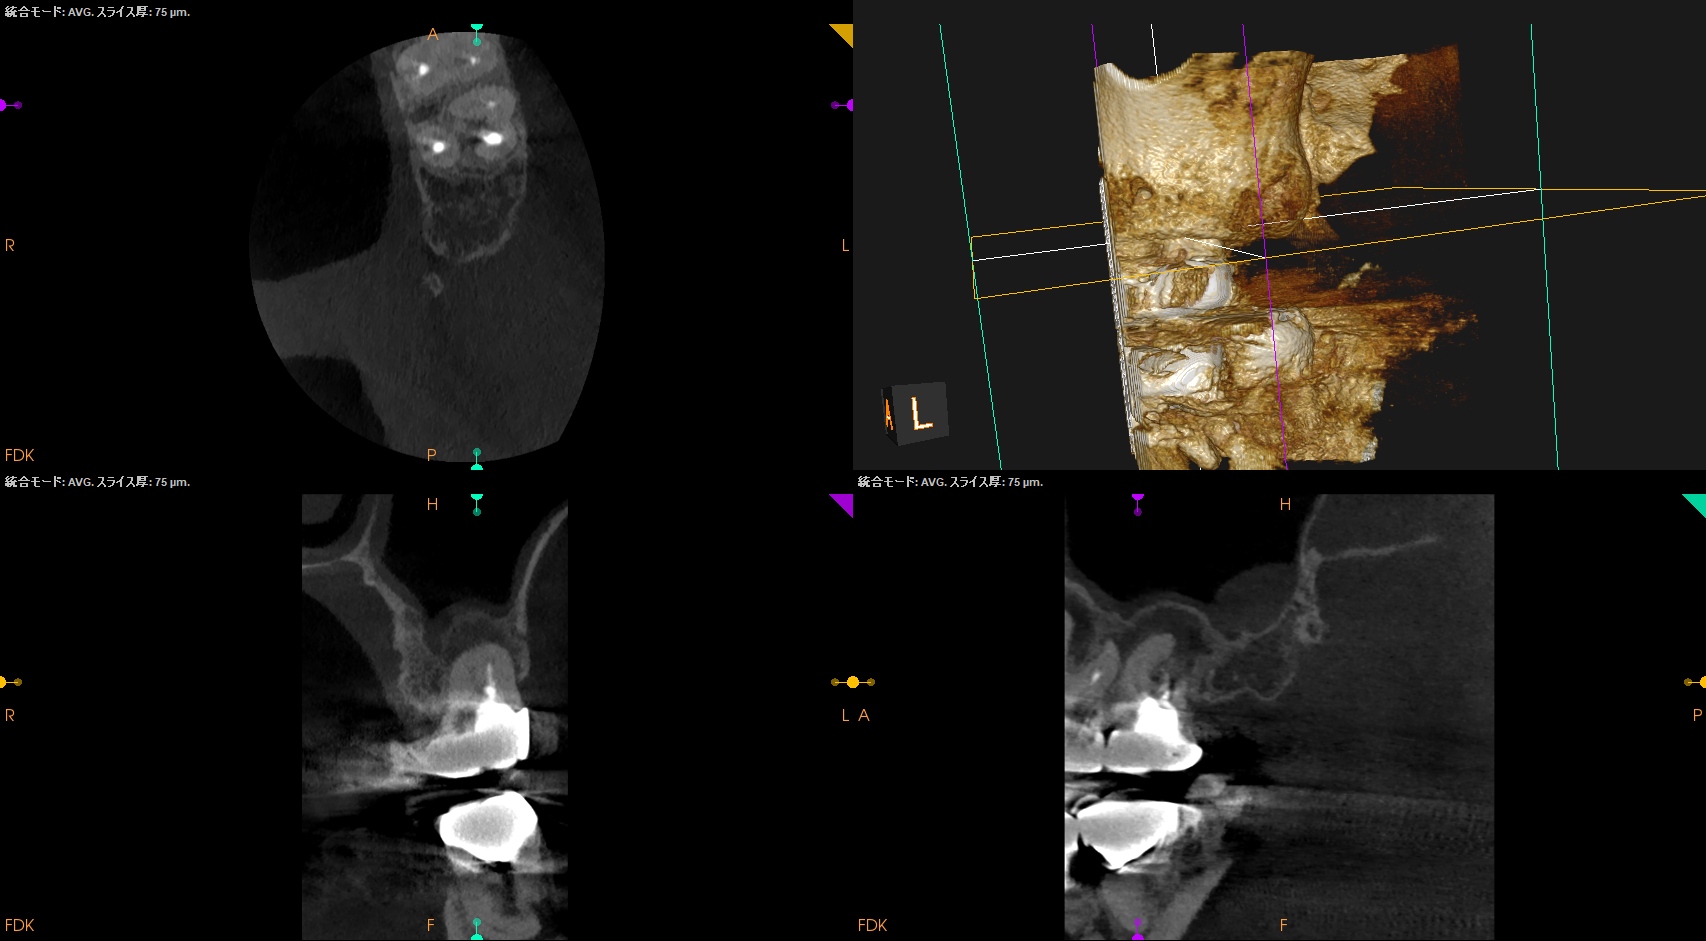

この臨床的事実をなんとかCBCTを使用して明らかにできないだろうか?と私は常々考えてきた。

今日はCaseを通じてそれを示してみたい。

術後のPA, CBCTは以下である。

MB1

MB2

DB

P

問題はないだろう。